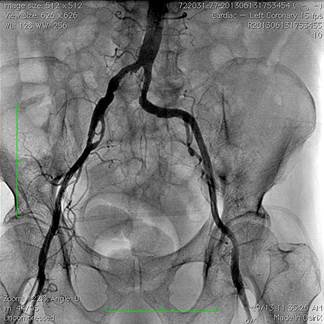

Các thăm dò trước thủ thuật thay van động mạch chủ qua da bao gồm: xét nghiệm công thức máu, hoá sinh máu, điện tâm đồ, siêu âm tim qua thành ngực và qua thực quản, chụp động mạch vành và chụp động mạch đùi cản quang, chụp cắt lớp vi tính đa dãy (MSCT) động mạch chủ ngực – bụng, động mạch đùi chậu. Bệnh nhân có tình trạng thiếu máu nhẹ trước thủ thuật (Hb 98 g/L), chức năng thận bình thường (mức lọc cầu thận 98 mL/phút). Điện tâm đồ có hình ảnh bloc nhánh trái hoàn toàn, tăng gánh tâm thu thất trái. Kết quả siêu âm tim qua thành ngực cho thấy hẹp khít van động mạch chủ, diện tích lỗ van 0,636 cm2, chênh áp tối đa qua van động mạch chủ 67 mmHg, chênh áp trung bình 40,4 mmHg. Hở van động mạch chủ mức độ nhẹ. Đường kính vòng van động mạch chủ 25,2 mm, đường kính đường ra thất trái 24,3 mm, đường kính động mạch chủ ngang qua xoang Valsava 32 mm, đường kính động mạch chủ lên 24,7 mm. Chức năng tâm thu thất trái trong giới hạn bình thường (EF 65%). Đường kính thất trái cuối tâm trương 50 mm. Bệnh nhân có tăng áp lực động mạch phổi mức độ vừa (áp lực động mạch phổi tâm thu 45 mmHg). Chụp động mạch vành có hẹp 40% đoạn giữa động mạch liên thất trước, dòng chảy mạch vành tốt. Chụp cắt lớp vi tính 64 dãy động mạch chủ ngực-bụng cho thấy xơ vữa gây hẹp lan toả động mạch chủ. Động mạch chủ ngực, động mạch chủ bụng trên và dưới động mạch thận có khẩu kính bình thường, ngã ba chủ chậu không hẹp tắc. Hẹp khít động mạch thận hai bên. Động mạch chậu và động mạch đùi phải xoắn vặn, hẹp lan toả, đường kính động mạch đùi phải chỗ hẹp nhất khoảng 5 mm. Động mạch chậu và động mạch đùi trái không hẹp, đường kính động mạch đùi trái chỗ hẹp nhất 6,5 mm. Động mạch dưới đòn trái không hẹp, tắc.

Hình 1: Đánh giá động mạch đùi – chậu bằng phim chụp cản quang

Mặc dù các van sinh học thế hệ mới ngày càng có kích thước nhỏ gọn hơn, tuy nhiên tỉ lệ biến chứng mạch máu vẫn còn cao (khoảng trên 10%)5. Đo kích thước và đánh giá tình trạng hẹp, tắc, xoắn vặn, vôi hoá của mạch máu động mạch đùi, động mạch chậu, động mạch chủ bụng trước thủ thuật, theo phim chụp cắt lớp vi tinh đa dãy, phim chụp mạch cản quang, và siêu âm mạch máu, giữ vai trò rất quan trọng trong việc giảm tỉ lệ biến chứng mạch máu. Đối với bệnh nhân của chúng tôi, đường kính động mạch đùi trái chỗ hẹp nhất là 6,5 mm, trong khi động mạch đùi-chậu phải xoắn vặn và hẹp lan toả. Khác với van Edwards-Sapien, không thể tiến hành đặt CoreValve xuôi dòng qua đường mỏm tim. Do vậy, chúng tôi cũng đã tiến hành đo đạc để sẵn sàng đặt van qua đường động mạch dưới đòn phải hoặc qua đường mở ngực tối thiểu, trong trường hợp không thể tiến hành qua đường động mạch đùi. Tuy nhiên, kích thước động mạch đùi-chậu trái của bệnh nhân hoàn toàn tương thích cho sheath 18 French và thủ thuật được tiến hành thuận lợi, không gặp khó khăn nào liên quan đến đường can thiệp. Dụng cụ đóng động mạch chuyên dụng Perclose (hãng Abbott, Hoa Kỳ) cho phép cầm máu vết chọc mạnh nhanh và hiệu quả. Bệnh nhân của chúng tôi hoàn toàn không gặp phải một biến chứng nào liên quan đến đường vào mạch máu.